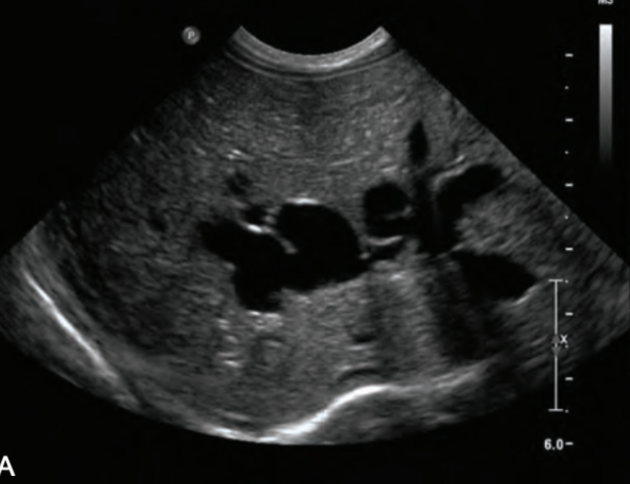

biliary ductal dilatation

“bil-dil” is ductal dilation due to obstruction

SONO: “bil-dil”

“shot gun” barrel appearance

parallel to the PVs

intrahepatic ducts >2mm

extrahepatic dilation occurs before intra

??

biliary ductal dilatation (“bil-dil”)